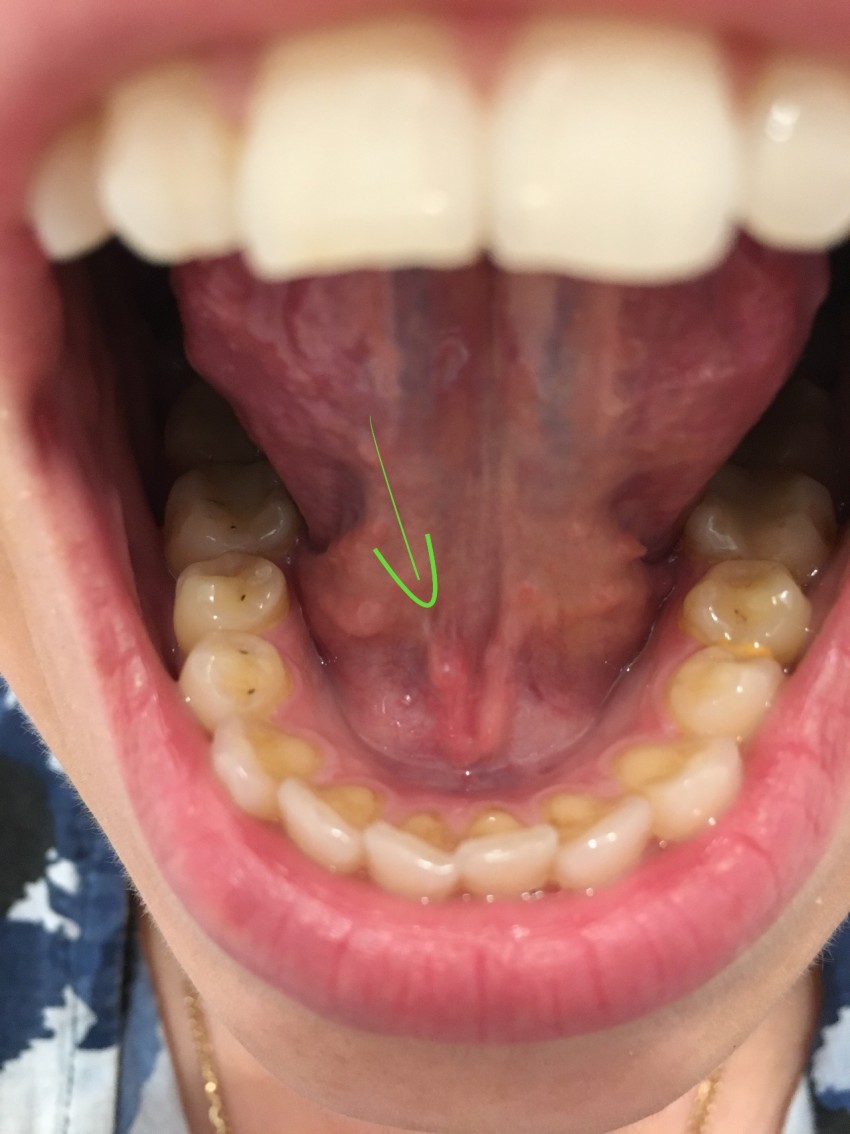

Фото прыщей на языке

Осмотрев появившийся бугорок в зеркале при хорошем освещении, можно попытаться определить, что именно за прыщ образовался на языке, предварительно оценив свое поведение в повседневной жизни и общее состояние здоровья. Небольшая царапина или воспаление сосочка на языке обычно проходят самостоятельно, главное — не пытаться их срезать, выдавливать или откусывать.